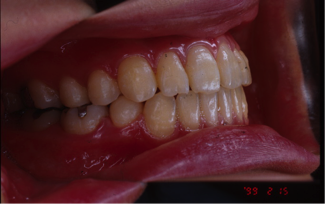

開咬(かいこう)

24歳/女性

悩み:前歯が噛めない

奥歯は噛み合っていても上と下の歯に隙間が空いてしまう状態

治療期間:約3年

治療前

治療後

前歯で噛む事が出来ないとの悩みから来院された患者様で、開咬症例ではあるのですが突出傾向があったため、小臼歯4本抜歯をする治療方針で約三年ほどかかって治療いたしました。治療後にはきちんとものが噛めるようになり、約三年間の頑張りが報われましたと喜んで頂けました。